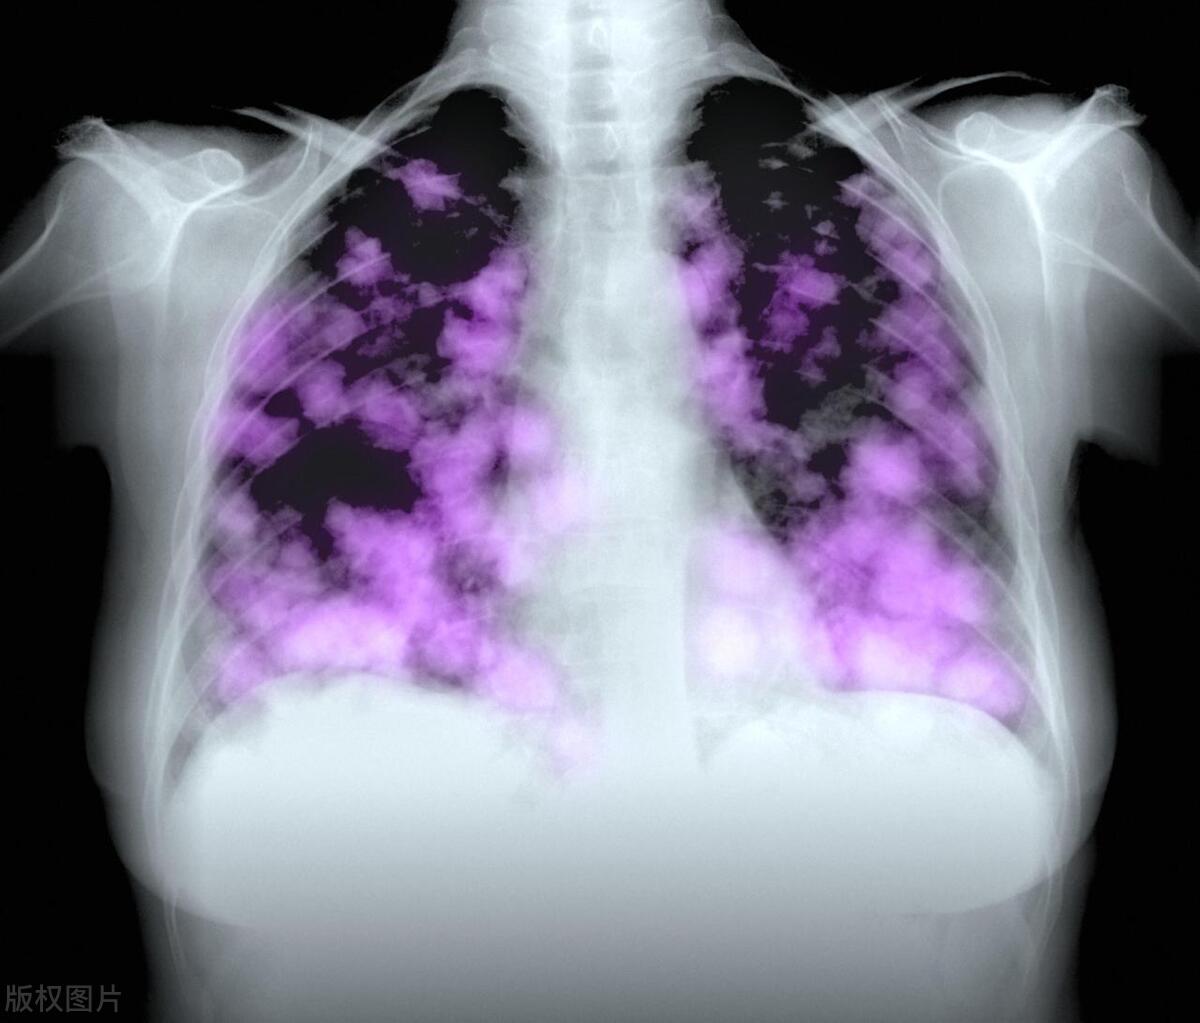

影像学检查: 定期进行影像学检查,如CT扫描、X光和MRI,有助于监测肿瘤的生长和变化。这些检查可以提供有关肺癌是否有进展的信息。